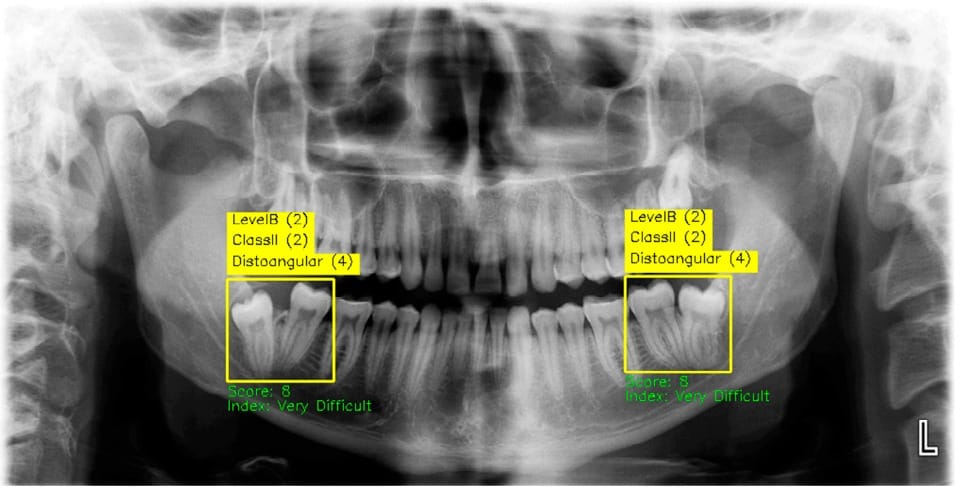

"Yapay zekayı sürece dahil etmemizin temel sebebi; insan gözünün kaçırabileceği milimetrik detayları yakalamaktır. Elde ettiğimiz veriler, yapay zekanın %99’a varan doğruluk oranlarıyla teşhis yapabildiğini gösteriyor. Bu, tıpta neredeyse 'sıfır hata' diyebileceğimiz bir devrimdir."

Türkiye’de uzman sayısı oldukça az olan Ağız, Diş ve Çene Radyolojisi branşının kritik önemine değinen Bulut, bu alanın çene ve yüz bölgesindeki karmaşık patolojilerin tespitinde anahtar rol oynadığını belirtti. Yapay zekânın, bir uzmanın yıllar içinde edindiği tecrübeyi standart bir diş hekimine aktarabilecek bir köprü vazifesi gördüğünü ekledi.

Kontrol ve imza yetkisinin her zaman insanda kalacağını belirten Bulut, özellikle nadir görülen hastalıklar ve sinüs patolojileri gibi uzmanlık gerektiren durumlarda YZ analizlerinin yanlış tedavilerin önüne geçeceğinin altını çizdi.